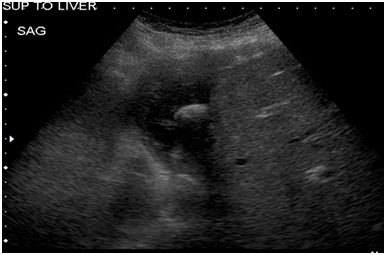

Due to concerns for a fistulous communication between the pericardial and peritoneal cavities, the procedure was begun in the chest first to reduce the chances of cardiac tamponade from pneumopericardium. A subxyphoid pericardial window was performed and a 32fr chest tube was placed. On laparoscopy, significant adhesions were noted above the liver (Figure 3). Dissection above the liver was challenging given the chronic inflammation and the proximity of the abscess cavity to the hepatic veins. The abscess cavity in the sub diaphragmatic space was entered and the stone was found (Figure 4). The remnant abscess was drained and a flat Jackson Pratt drain was left in the cavity after irrigation. The stone was retrieved using an end catch bag (Figure 5). The patient’s postoperative recovery was uneventful. The pericardial drain was removed prior to discharge and his abdominal drain was removed in clinic. He was sent home with a 2week course of ceftriaxone.

Figure 3 Significant adhesions above the liver.